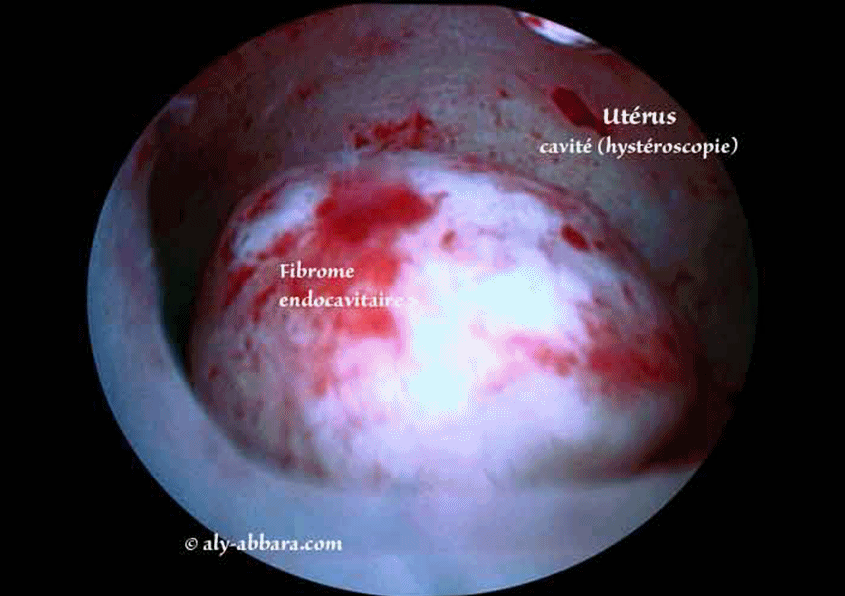

Fibrome endocavitaire, sous muqueux pédiculé (classe 0 de FIGO) du fond de l'utérus

Images montrant un fibrome utérin endocavitaire, sous muqueux pédiculé (classe 0 de FIGO) de 14 x 12,3 x 7 mm de diamètre, soit 0,63 cm3.

Il s'agit d'images permettant de comparer l'aspect échographique à l'aspect anatomique hystéroscopique avec grossissement ; puis l'image qui suit immédiatement montre l'aspect hystéroscopique du fond la cavité utérine, et en particulier, le site d'insertion du pédicule de ce fibrome déjà sectionné par myomectomie hystéroscopique à l'aide de l'anse de résection mono-polaire.